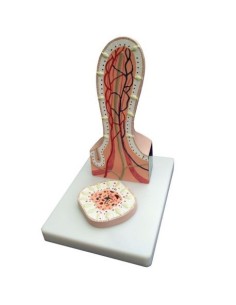

Modèle anatomique de néphron avec vaisseaux sanguins, agrandi 120 fois k10/1